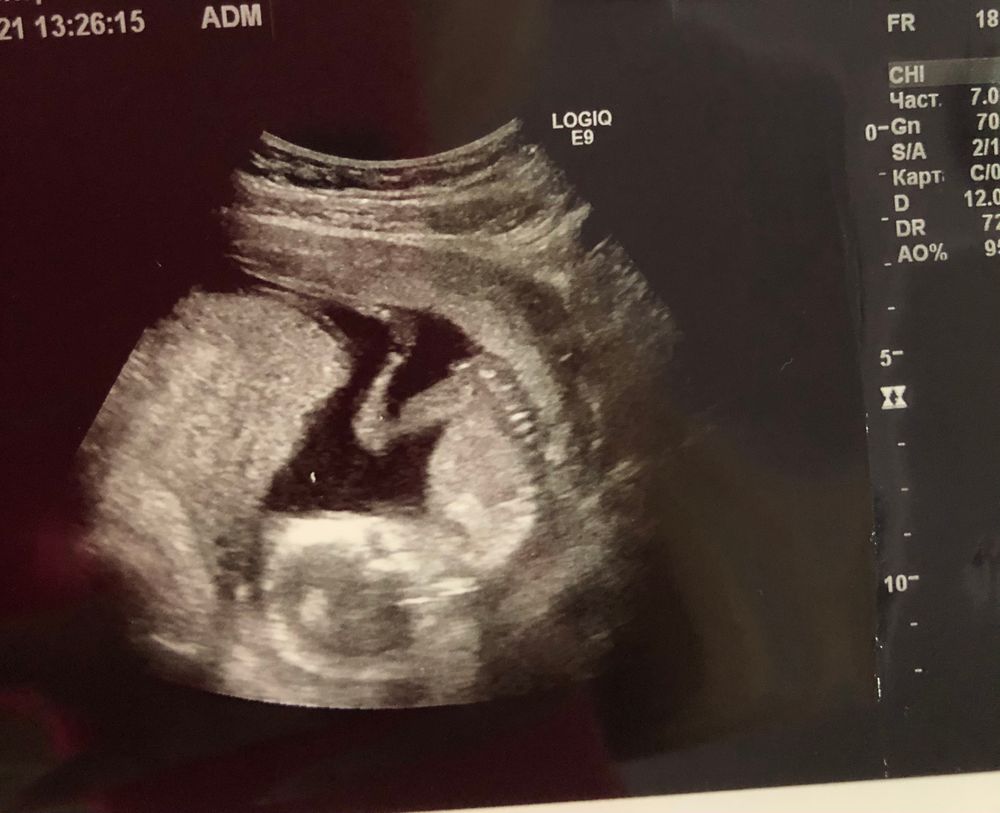

это 12 недель

Ну так по фото в 12-недель,девчушка у вас.Бугорок лежит,как и у нас.Поздравляю!!!!

А почему по половому бугорку не сработало? Бугорок девчачий в 12 недель